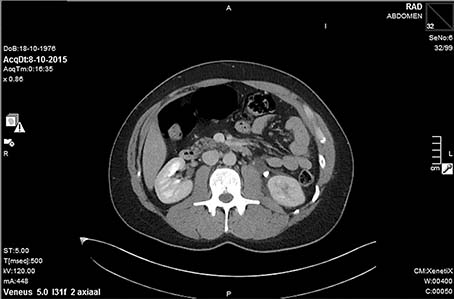

Een 38-jarige man komt op het spreekuur van de huisarts vanwege hevige buikpijn sinds een dag. De patiënt beschrijft de buikpijn als intermitterende, hevige darmkrampen en wisselt periodes van bewegingsdrang af met periodes waarin een foetushouding het meeste comfort geeft…